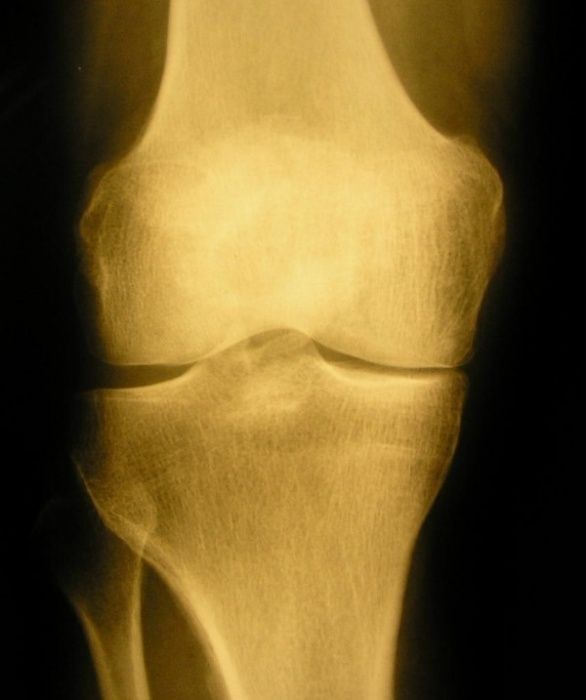

Zusammengefasst: Es gibt unterschiedliche Auslöser und Ursachen, das Ergebnis sind eine Funktionsverschlechterung und Knorpelschwund. Mit Hilfe einer Bilddiagnostik lässt sich sehr genau festhalten, wie diese Knorpelschicht dünner wird.

Von einer Arthrose wird erst gesprochen werden, wenn in der bildhaften Diagnostik eine Veränderung der Knorpelschicht des Gelenks sichtbar wird. Je nach Ausprägung der Knorpelveränderung wird sie mit dem Grad I (Aufrauung der Oberfläche) bis Grad IV (Knorpelverlust mit brachliegender Knochenoberfläche) bezeichnet.